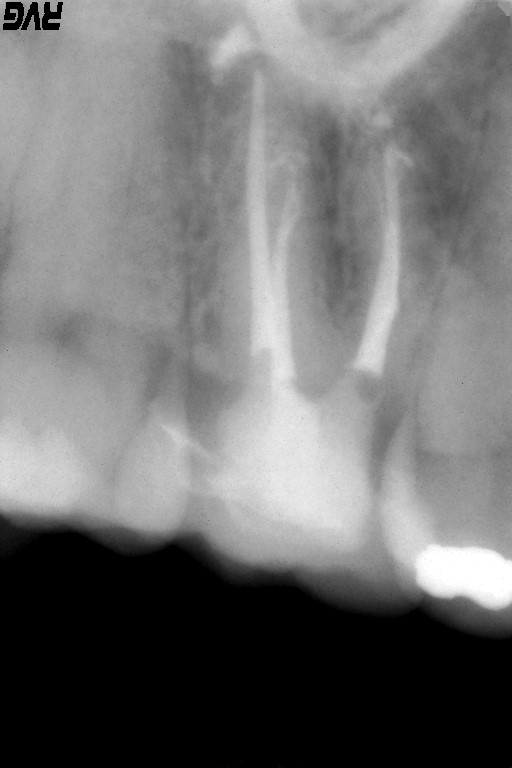

患歯は、以前の治療で神経の近くまで処置をしていたため、歯髄に感染を起こして根尖部から腐敗した物質や、細菌が根尖周囲の組織を破壊しているため大きな骨欠損を確認できます。

根尖までの長さや根尖孔の太さを確認するためにファイルを入れてレントゲン撮影を行います。

根管形成が終わり、根管洗浄を十分に行い、バイオセラミックによる根管充填を行ないました。

根尖部よりバイオセラミックが出ているが、臨床的には何も問題はありません。この語、骨が再生されるまでには数ヶ月時間かかります。